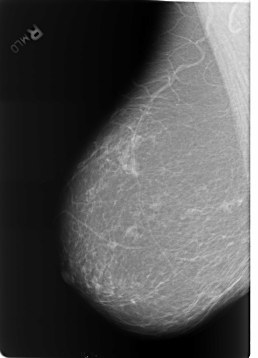

Digital Database for Screening Mammography

Volume: benign_without_callback_01 Case: B-3253-1

B_3253_1.RIGHT_MLO

filename B-3253-1

DATE_OF_STUDY 11 8 1998

PATIENT_AGE 61

FILM_TYPE REGULAR

DENSITY 2

DIGITIZER LUMISYS LASER

RIGHT_MLO LINES 5728 PIXELS_PER_LINE 4120 BITS_PER_PIXEL 12 RESOLUTION 50 NON_OVERLAY

FILE: B_3253_1.LEFT_MLO.OVERLAY

TOTAL_ABNORMALITIES 3

ABNORMALITY 1

LESION_TYPE CALCIFICATION TYPE LUCENT_CENTER DISTRIBUTION N/A

ASSESSMENT 2

SUBTLETY 5

PATHOLOGY BENIGN_WITHOUT_CALLBACK

ABNORMALITY 2

ABNORMALITY 3